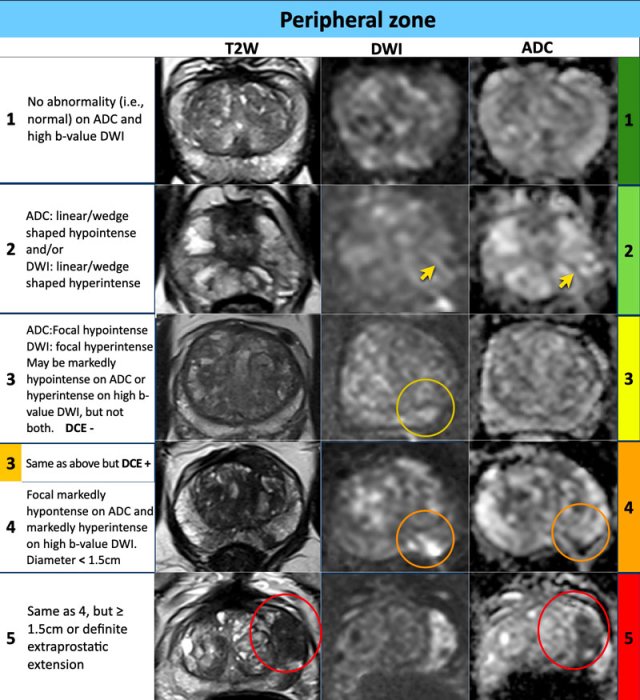

Peripheral zone

PI-RADS

For the peripheral zone the DWI/ADC is the primary determining sequence to assign the PI-RADS assessment category.

Peripheral zone - DWI/ADC category 1

- No abnormality visible on ADC and high b-value DWI.

Peripheral zone - DWI/ADC category 2

- Linear/wedge shaped configurations with hypointensities on ADC and/or linear/wedge shaped hyperintensities on high b-value DWI.

Peripheral zone - DWI/ADC category 3

- Focal (discrete and different from the background) hypointensity on ADC and/or focal hyperintensities on high 3 b-value DWI

- May be markedly hypointensity on ADC or markedly hyperintensity on high b-value DWI, but not both.

- A category 3 lesion remains a PI-RADS score 3 if there is no focal enhancement (negative), but becomes a PI-RADS score 4 if the enhancement is focal.

Peripheral zone - DWI/ADC category 4

- Focal markedly hypointensity on ADC and markedly hyperintensity on high b-value DWI

- <1.5cm in greatest dimension.

Peripheral zone - DWI/ADC category 5

- Same as as assessment score 4 but ≥1.5cm in greatest dimension or

- Definite extraprostatic extension (EPE) or invasive behavior.

Examples of PI-RADS 1-5

Examples of PI-RADS scores 1-5 are given in the table.

In the peripheral zone, the PI-RADS assessment category of a lesion is determined primarily on DWI/ADC and correlated to T2W- and DCE-images.

In the peripheral zone an equivocal or indeterminate lesion (category 3) is assigned to PI-RADS category 4 if DCE is positive, i.e focal or earlier contrast enhancement.

The lesion remains assigned to PI-RADS category 3 if the DCE is negative, i.e. no early enhancement or diffuse enhancement and not corresponding to the focal T2W/DWI lesion or focal enhancement corresponding to BPH.